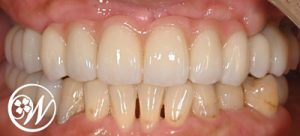

治療後の変化

・固定式の歯となり、しっかり噛める状態を回復

・口元の見た目が整い、審美面も改善

・仮歯期間で調整を行ったことで、最終補綴へスムーズに移行